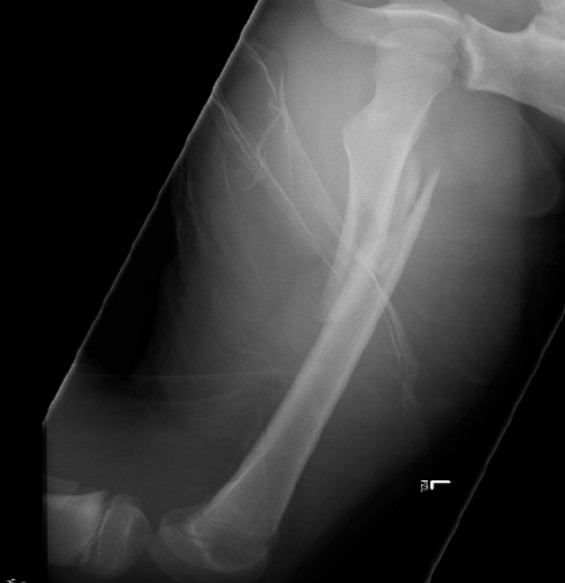

Paediatric femoral shaft fracture transfer

An 11-year-old girl presents to your rural emergency department after a car accident. An X-ray of the left femur is …